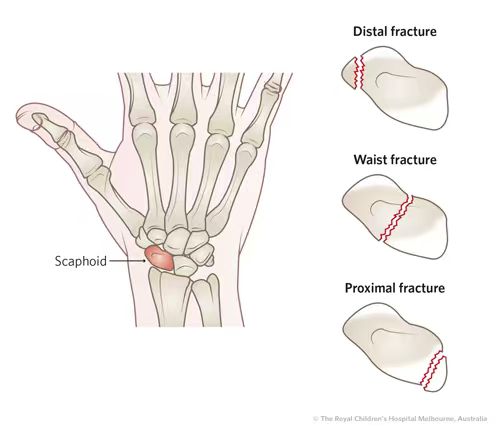

2.舟状骨骨折

位于大拇指下方的舟状骨在手腕撑地时极易受损。这种骨折非常棘手,因为舟状骨的血液供应相对匮乏。这种骨折极难愈合,处理不当可能导致永久性的关节炎或骨坏死。(许多网球和高尔夫运动员因这种隐匿性骨折而导致职业生涯巅峰缩短,因为该部位关系到手腕的精细转动。)